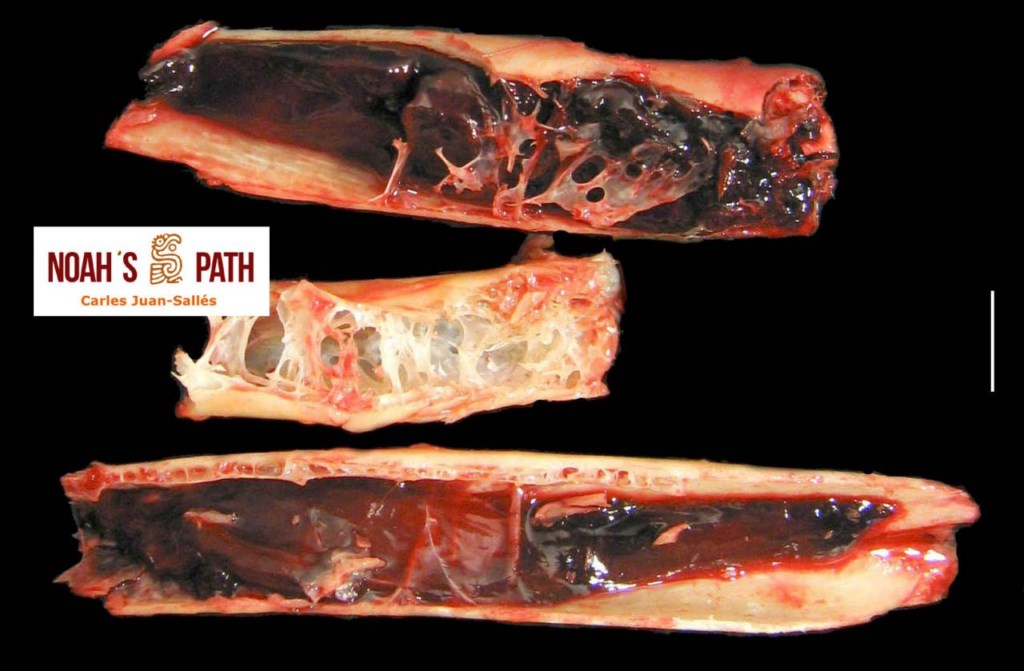

El examen post mortem ofrece una oportunidad única de acceso a todos los tejidos del paciente para diagnóstico de las causas de enfermedad y muerte, y por lo tanto es esencial para medicina preventiva y curativa en grupos de animales, seguimiento de casos, estudios sobre enfermedades, control de zoonosis, medicina de la conservación, y patología forense. En Noah's Path pensamos que un examen post mortem de este tipo de fauna debería ser realizado siempre que sea posible por patólogas/os especializadas/os con el fin de obtener el máximo de información y obtener las muestras más adecuadas.